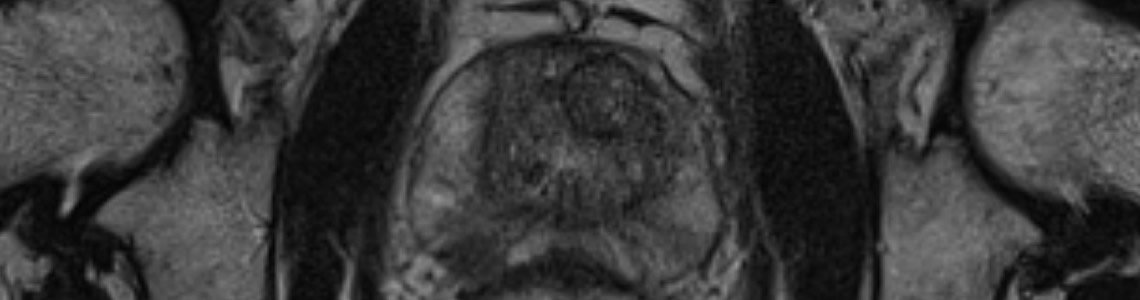

Multiparametrische MRT Prostata (mpMRT)

Die multiparametrische MRT der Prostata ist ein modernes und genaues Verfahren zum Nachweis bzw. Ausschluß von Krebsherden in der Prostata und ggf. zur Vorbereitung einer zielgenauen Biopsie.

Die MRT-Prostatographie ist ein modernes Verfahren zur Diagnostik des Prostatakarzinoms. Mit Hilfe der multiparametrischen MRT-Untersuchung können bösartige Tumorherde in der Prostata entdeckt und genau lokalisiert werden, sodass der Urologe, wenn notwendig, eine gezielte Gewebeprobe entnehmen kann. Außerdem können bei der Untersuchung gutartige und entzündliche Erkrankungen unterschieden werden. Die Untersuchung wird bei Patienten mit steigendem PSA-Wert, mit erhöhtem familiärem Risiko oder nach einer negativen Gewebeentnahme bei weiterhin erhöhtem PSA-Wert durchgeführt.